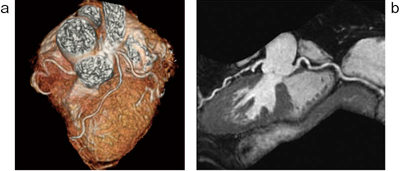

4.3D Heart

冠動脈の狭窄評価にはMDCTが一般的だが,小児や高度石灰化の患者,腎機能が低下している患者において,MRIを用いた非侵襲的な冠動脈スクリーニングを行う施設は増加傾向にある。

“3D Heart”は,マルチスラブ法と横隔膜同期を用いたスラブトラッキング併用の非造影冠動脈撮像法であり,データ収集は3D FIESTA法とIR prep併用のFGRE法の2種類が選択可能である。従来法と比較して,マルチスラブ法やスラブトラッキングを用いた3D Heartでは,撮像中の患者の呼吸変化や心拍変動による画質劣化を軽減し,より安定した撮像が可能となっている。その結果,遠位部の血管描出能や左回旋枝の描出能が向上し,検査の成功率も上がっていると報告されている1)(図4)。

図4 3D Heartによる冠動脈撮像

a:ボリュームレンダリング像(Advantage Workstation使用)

b:リフォーマット像